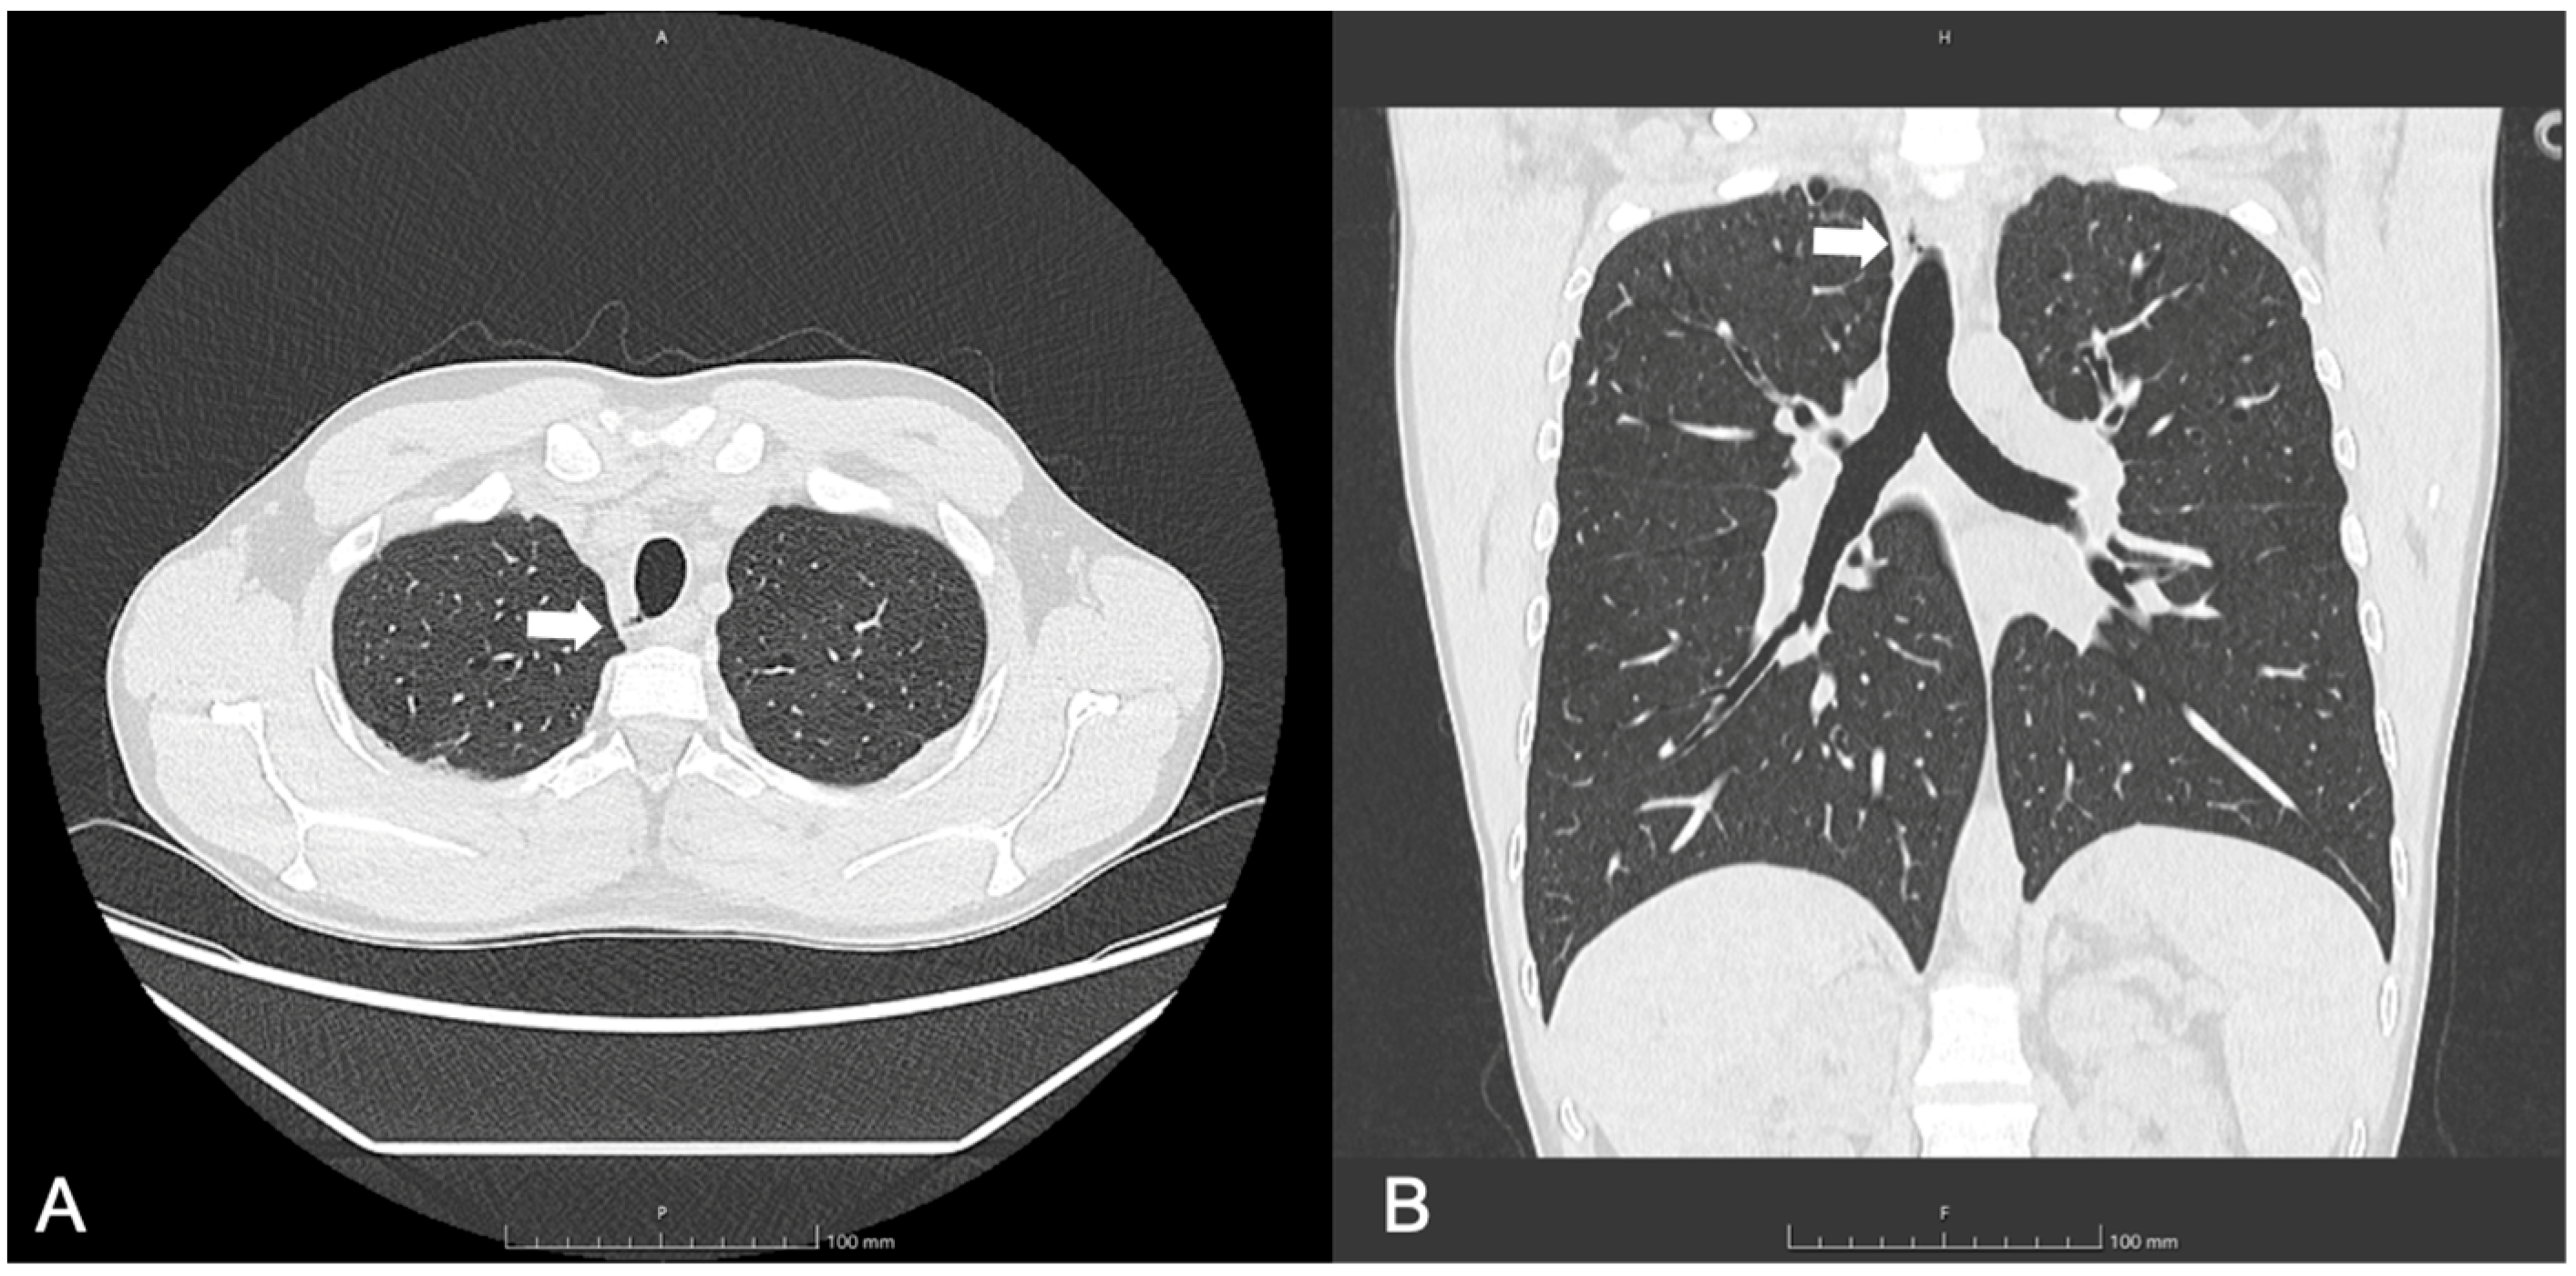

3.1. Patient 1

| 30, M | F508del/ E585X | SA, PA | 73 | 36 | 2, 10 mm, right posterolateral at T2 level | Yes | Visible radiologically and endoscopically | Bronchoscopy after 6 months: stable TD; occurrence of punctiform paracarenal TD |